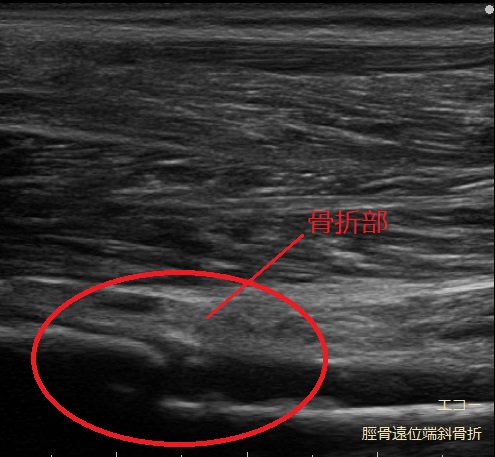

超音波(エコ-)検査は、骨・靭帯・筋肉・腱などの病態を診る検査装置です。

レントゲン画像には映りにくい筋肉や腱、靭帯などの状態に加え、骨の様子もあわせて確認できます。